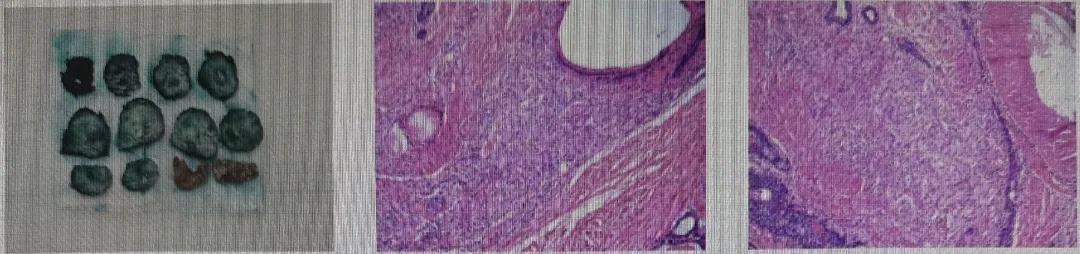

前列腺穿刺(2024-9-10)

在局麻下行超声引导下经会阴前列腺穿刺活检术,取出长约2cm组织条十三条送检。

术后病理:前列腺腺泡腺癌,Gleason评分如下:

机器人辅助根治性前列腺切除术

泌尿外科团队联合肿瘤科、放疗科及医学影像科等多学科专家,结合最新循证医学证据讨论后,认为患者原发灶切除时机成熟。患者于2025-4-10接受机器人辅助操作腹腔镜下前列腺癌根治性切除术,术后病理:前列腺腺泡性腺癌(ypT2N0M1)。

8.png